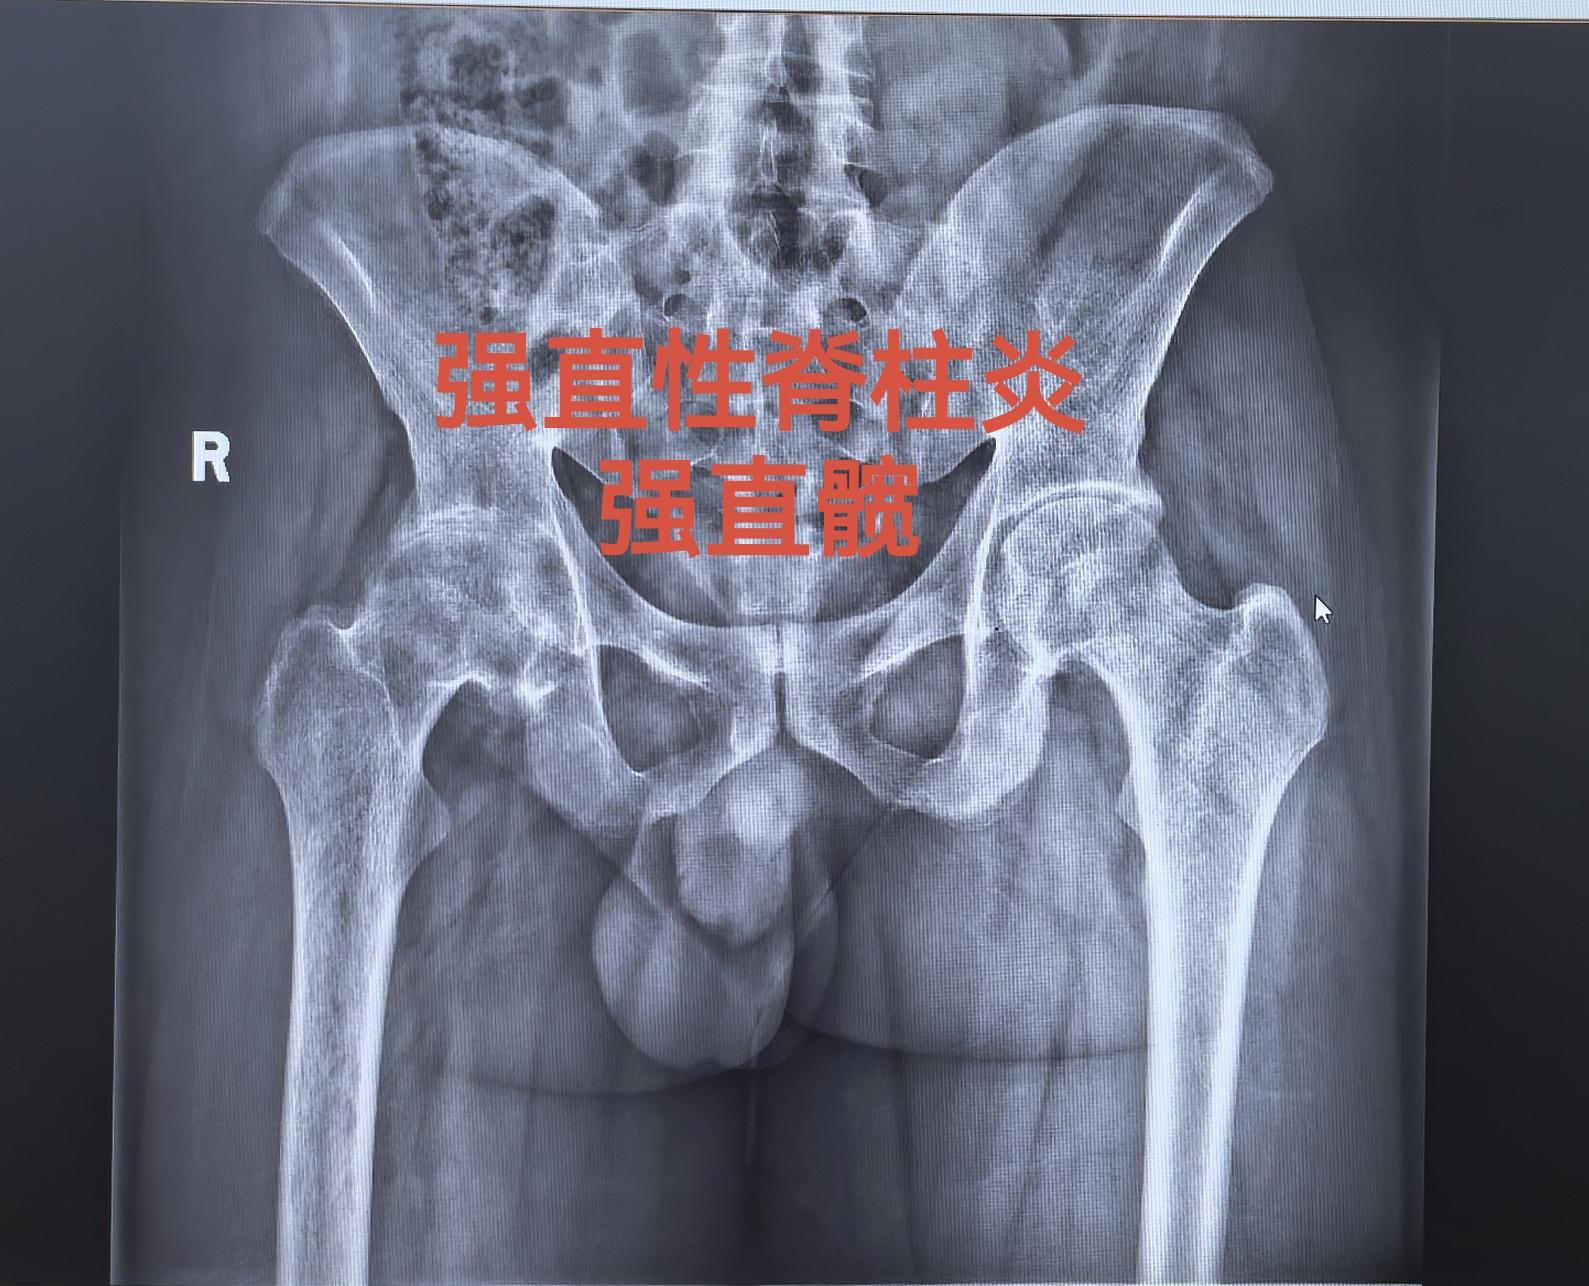

强直髋。强直髋,髋关节无活动度,如有条件,尽早手术,拖得越久,软组织越...